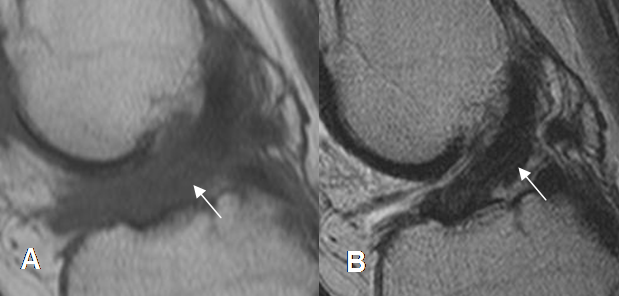

Fig 109. Fibrosis del LCA.

A: RM sagital en T1. Alteración en la señal del LCA, que indica patología.

B: RM sagital en T2. El LCA está integro, pero engrosado por fibrosis residual.